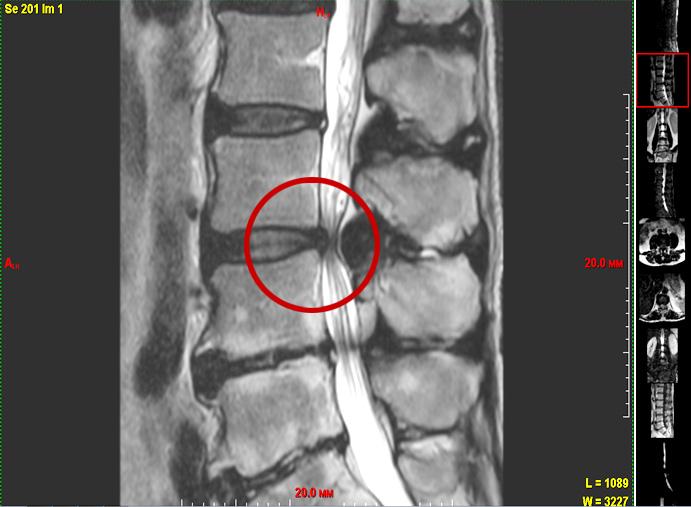

Грыжа диска

— Оно уменьшается по объему и перестает выполнять роль амортизатора. Нагрузка начинает падать на фиброзное кольцо, которое сзади наиболее тонкое. В этом месте оно быстрее трескается, и в эти трещины начинает выдавливаться пульпозное ядро. Если оно выпячивается немного, до 6 миллиметров, мы говорим о протрузии (выпячивании). Если происходит выпадение грыжи диска — это пролапс.

— Оперируем мы тогда, когда консервативное лечение не приносит результата. Чаще всего, когда или грыжа диска сдавила нервный корешок, или дугоотростчатый сустав значительно увеличился, или есть массивная гипертрофированная желтая связка. Т. е. когда идет компрессия структур спинного мозга или его корешков.

Говоря о рецидивах, хочу отметить, что очень сложно отличить, это рецидив или рубцовый процесс после операции. На МРТ разницы практически нет. Когда у пациента, у которого уже была операция, на том же уровне мы находим какие-нибудь «штуки», если нет строгих показаний к новой операции, мы пробуем консервативное лечение. Получили результат — замечательно. Потому что, допустим, в заключении МРТ нам написали рецидив, большой секвестр (участок омертвевшей ткани — прим. авт.), а мы заходим и, кроме рубцов, ничего не находим. Естественно, делаем декомпрессию, все рубцы рассекаем и прочее. Но если у человека уже пошло рубцевание, каждая последующая операция будет добавлять еще рубцов. Это склонность к келоидозу. Поэтому каждый раз, когда мы думаем, предлагать человеку операцию или нет, пытаемся оценить все возможные варианты. Если есть малейший шанс обойтись без операции, мы не бежим в операционную.